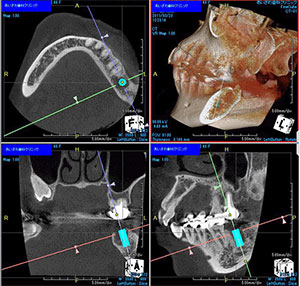

インプラント治療を成功させるためには手術前に正確な情報を得てシミュレーションを行い、正確で安全な手術を行う事が重要です。しかし、従来のインプラント手術は歯科医師の経験や勘に頼った部分が多くありました。

そこで当院では、CTやシミュレーションソフトを活用し、正確なデータに基づく治療を実践しています。

CTとは、立体的(三次元)に骨の状態や神経の位置を把握できる特殊な撮影装置です。

二次元のレントゲン(歯科医院にある通常のレントゲン)では見えなかった事、分からなかった事が、歯科用CTなら正確な診査と診断ができ、安全性と治療のクオリティーを高めることが可能となります。

医療において「見える」「見えない」は治療クオリティーに大きな差が出ます。ましてや外科手術を伴うインプラントにおいてはなおさらです。

CT画像をシミュレーションソフトに取り込むことで更に「安全・確実」な治療が実現できるようになりました。

インプラントを成功させる為に一番重要な事は、いかに正確な情報を手術前に取得できるかにかかってきます。これを可能にしてくれるツールがシミュレーションソフトです。

シミュレーションソフトを簡単に説明しますと、今までは実際に手術をし、歯茎を切開してみなければ分らなかった事が、手術前に分ってしまうことが特徴的です。

骨の厚さや神経、血管の位置などですね。これが事前に分ることで、手術前に様々なシミュレーションが可能になります。

どの部分に、どの方向に、どのくらいの深さまで、どのサイズのインプラントを埋入するだとか、ここには神経、血管が走っているので、避けてインプラントを埋入しようなどです。